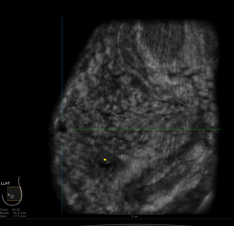

Breast ultrasound is often used to evaluate breast problems that are found during a mammogram or on

physical exam. Ultrasound helps distinguish normal findings like cysts or fat lobules from suspicious

breast changes that need biopsy. In someone with a suspicious breast mass, ultrasound can be used to

look for enlarged lymph nodes under the arm. Breast ultrasound is often used to guide a needle to biopsy

breast lesions and abnormal lymph nodes.To know more Click Here